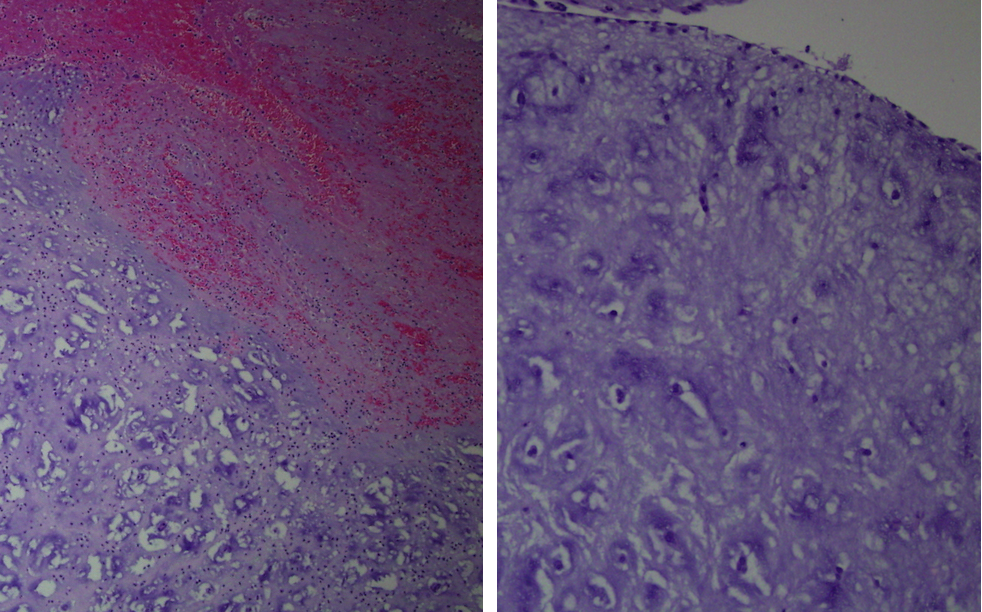

The histopathology of the mass was reported as tumor fragments composed of cords and isolated cuboidal cells and few elongated and stellate cells. Stroma contains myxoid material and hemorrhage. These findings are consistent with myxoma (Figures 7).

Figure 7: Histopathology of mass showing cords and isolated cuboidal cells and stellate cells. Stroma contains myxomatous material.